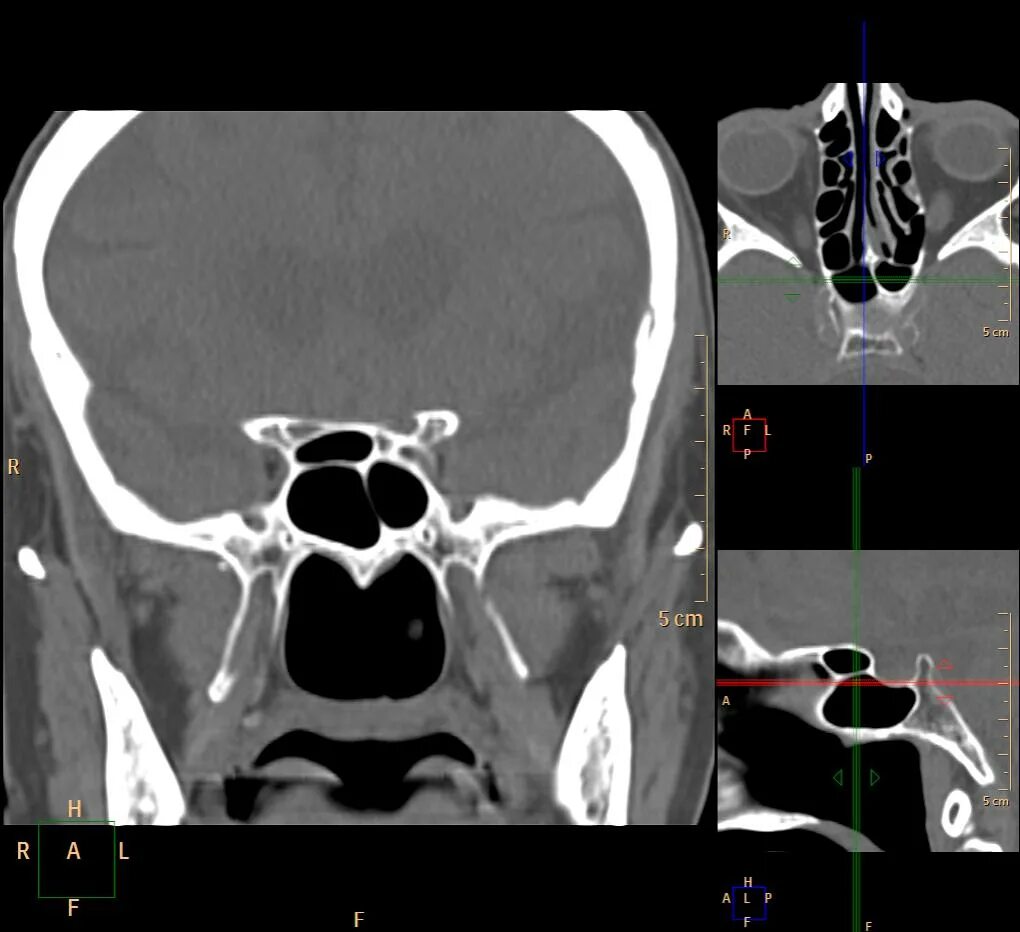

Содержимое в основной пазухе